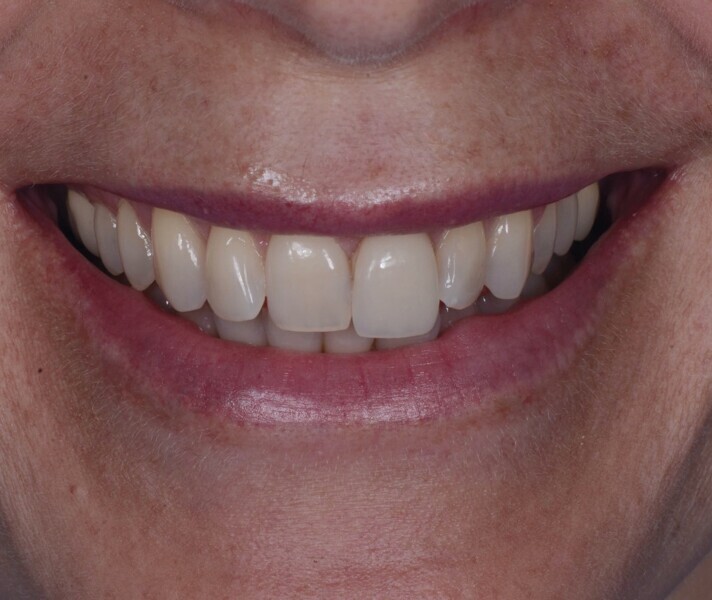

Une patiente de 42 ans est adressée au cabinet pour le remplacement de son incisive centrale supérieure gauche (dent 21) qui est à l’origine de douleurs. Un antécédent de traumatisme dentaire remontant à l’adolescence est rapporté. La ligne du sourire de la patiente est normale, mais la dent 21 est égressée (Fig. 1) La gencive présente un biotype raisonnablement épais et le feston gingival est très marque.

Fig. 1a : Vue préopératoire extraorale : lèvres au repos a

Fig. 1b : Vue préopératoire extraorale : lèvres au sourire

Fig. 21a : Sourire avant le traitement.

Fig. 21b : Sourire après le traitement.

Lors du suivi a cinq ans, on ne peut que constater le résultat esthétique maintenu (Fig. 21). La radiographie montre un niveau osseux stable et une connexion étroite entre l’implant et le pilier (Fig. 22).